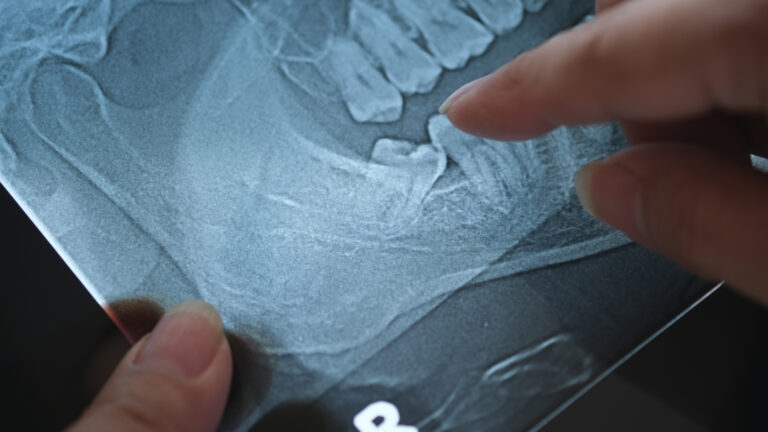

1. Consultation & Examination: Your dentist or oral surgeon will evaluate your teeth using X-rays to determine if extraction is necessary.

A surgical extraction is performed when a tooth is not easily accessible or fully erupted. It involves making an incision in the gum to remove impacted, broken, or complex-rooted teeth.

A surgical extraction is a procedure used to remove a tooth that is not easily accessible or has not fully emerged from the gum line. This is often necessary for impacted teeth, broken teeth, or teeth with curved roots. Unlike simple extractions, which involve removing a visible tooth, surgical extractions require an incision in the gum to access the affected tooth.